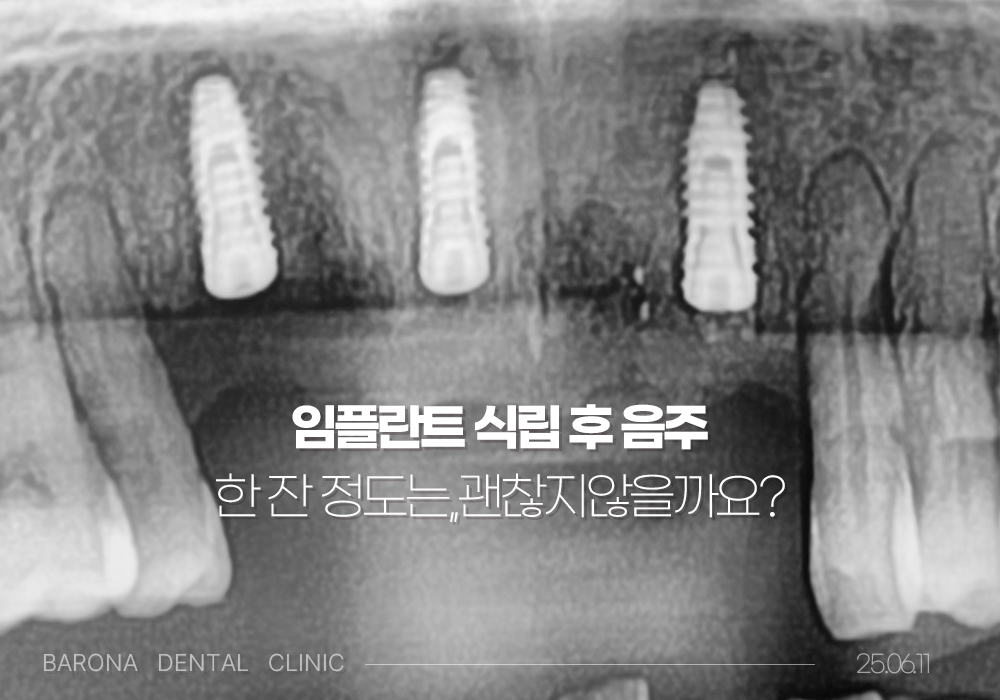

임플란트 식립 수술 후 음주

왜 피해야할까요?

"한두잔 정도는 괜찮지 않나요?"

라고 생각하시는 분들도 계신데